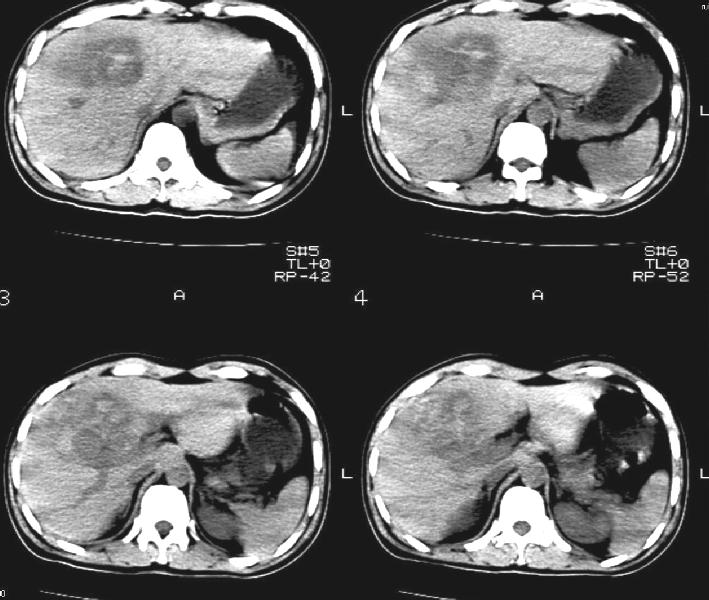

标题: CT11005:男,40岁,左股骨骨折术后10余天,现在感右上腹痛。

b超:右前叶不均质占位。是肿瘤出血还是肝挫伤?以前没有症状啊,10多天后腹部才疼痛。

肝挫裂伤伴血肿形成.

右侧胸腔积液,又有外伤史,肝脏混杂密谋影,考虑肝挫伤可能性大.

右侧胸腔积液,又有外伤史,肝脏混杂密度影,考虑肝钝性挫伤可能性大。

建议增强扫描